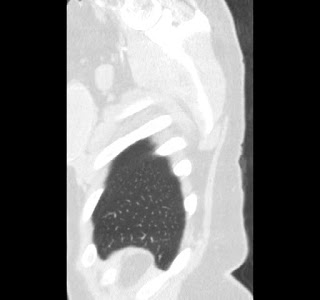

40 year old female. Breast implants 17 years ago, most likely Dow Corning. Symptoms from upper body for 6-7 years. Pain in breasts, ribs, back, neck. Skin rash. Headache and dizziness, weakness, numbness and vision disturbing. Sudden sleep episodes. Painful lymph-notes. These images are from 2010 and diagnose results were "No findings". Patient is scheduled for explantation in mid Feb. 2012